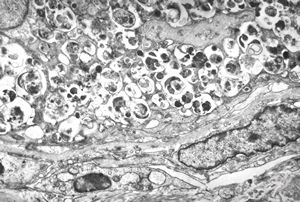

M,50y. | Pneumocystis carinii - lung